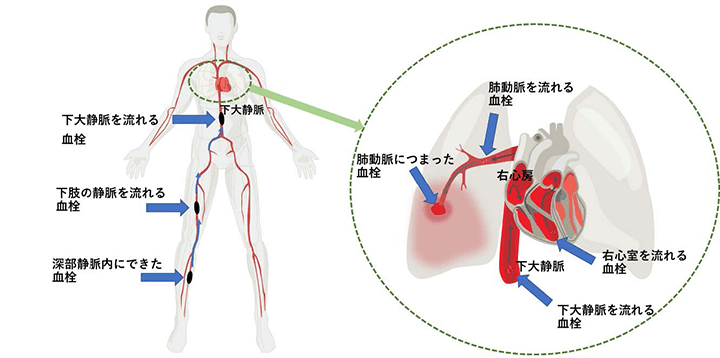

川崎 静脈血栓塞栓症浅田内科・循環器内エコノミークラス症候群。

4 エコノミークラス症候群 肺血栓塞栓症 に関するQ&A - 4 エコノミークラス症候群 肺血栓塞栓症 に関するQ&A -災害時の対応について一般社団法人日本呼吸器学会。

解剖生理学攻略ページ - この四コマ漫画を見ると ・エコノミー症候群 ・深部静脈血栓症 ・肺塞栓症Facebook。

川崎 静脈血栓塞栓症浅田内科・循環器内エコノミークラス症候群。

4 エコノミークラス症候群 肺血栓塞栓症 に関するQ&A - 4 エコノミークラス症候群 肺血栓塞栓症 に関するQ&A -災害時の対応について一般社団法人日本呼吸器学会。

4 エコノミークラス症候群 肺血栓塞栓症 に関するQ&A - 4 エコノミークラス症候群 肺血栓塞栓症 に関するQ&A -災害時の対応について一般社団法人日本呼吸器学会。

慢性血栓塞栓性肺高血圧症千葉大学大学院医学研究院 呼吸器内科学。

6.心房細動と血栓塞栓症心房細動について心臓・血管の話 - みやけ内科・循環器科。